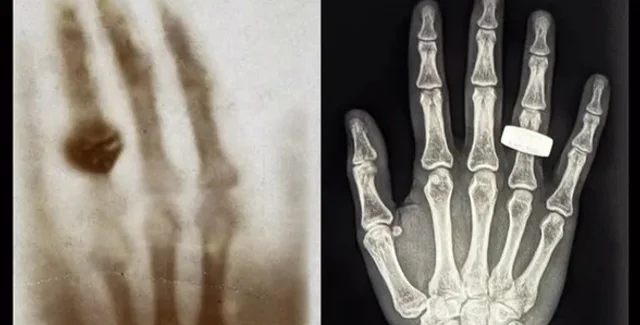

1895 року фізик Вільгельм Рентген уперше відкрив рентгенівські промені та зрозумів, що вони можуть бути корисними для медицини. У підсумку вчений зробив перший в історії рентгенівський знімок людського тіла. Це було зображення руки його дружини з обручкою. Через 130 років учасники місії Fram2 відтворили цю рентгенівську фотографію, але вже в космосі.

Перший рентгенівський знімок людини в космосі було зроблено під час місії Fram2 (праворуч). Екіпаж місії Fram2 вирішив віддати данину поваги найпершому рентгенівському знімку, на якому було зображено руку з кільцем (ліворуч)

Після того, як екіпаж місії Fram2 зробив рентгенівське зображення кисті руки, демонстрація цієї технології була продовжена серією інших діагностичних знімків, які включали передпліччя, таз, живіт і груди людини. Приватні астронавти також зробили знімки електроніки, щоб перевірити як можна використовувати рентгенівські промені для діагностики роботи приладів космічного корабля.